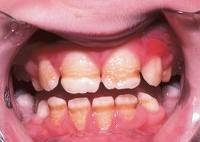

enamel hypoplasia

Front

-crowns have one or more rows of tiny pits and stains

enamel hypocalcification

-crowns may have pitting, grooves, or staining chalk white spots on middle -trauma to enamel during maturation phase